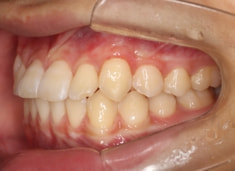

検査時のレントゲン分析では、上下顎の関係は、上顎の劣成長があり下顎前突傾向という値がでておりましたが、前歯ジャンプ後はフェイスマスクの効果もあり、上下顎の関係は正常化しています。

上顎が若干優位になっていますので、今後の下顎の成長のための貯金になっているくらいです。